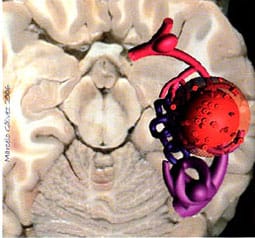

«Lo cierto es que (en una crisis) se inflaman las arterias, llegando a ocupar hasta cinco veces su espacio habitual en el cerebro y esto produce una fricción con los tejidos y nervios colindantes, que, a su vez, hace que se segregue una sustancia de los nervios para defenderse de esta agresión… Los nervios afectados suelen ser el del sistema digestivo, el de la vista, y el del oído…»

La teoría de las «arterias inflamadas» ha pasado ya a mejor vida hace unos años. Pocos defienden el origen vascular de la migraña. Las arterias de cualquier lugar del organismo se dilatan y contraen según órdenes del mando central neuronal pero, en ningún caso están inflamadas ni comprimen nada en el curso de una crisis migrañosa. Estaríamos listos…